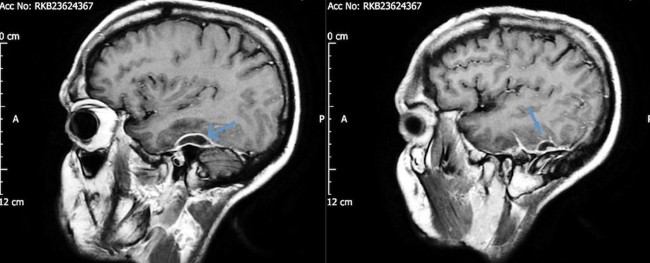

当为他进行头部CT扫描时,医生在脑部周围的组织中发现了充满脓液的囊肿,在他的一只耳朵内发现了引发感染的罪魁祸首:铜绿假单胞菌,一种危险的致病病原体。

在这种情况下,医疗团队认为患者的全部病情都来自铜绿假单胞菌感染,是被称为坏死性外耳炎(NOE,又称恶性外耳炎)的疾病,其影响外耳道(EAC)中的组织。